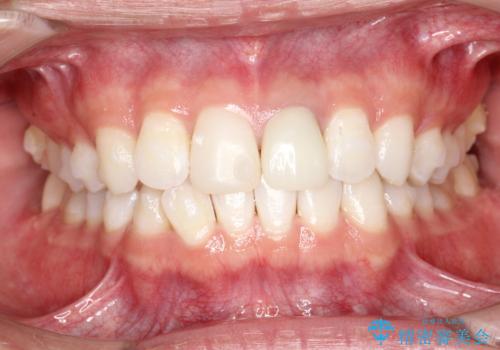

インビザラインによる矯正治療(非抜歯) 下の前歯の歯並びの改善

- 主に下の歯並びの改善を主訴としてご来院されました。

右下の犬歯と前歯が大幅に重なっているのと、歯の向きも大きく横に倒れています。この部位の正常な配列のためには、3次元的に大幅な移動が必要となりました。

インビザラインの特色を生かした歯牙移動計画を作成し、非抜歯にて治療を行いました。

概ね1年弱で治療が完了しました。

前歯の大きな3次元的移動を可能にするために、当院独自の工夫を随所に盛り込み、狙い通りの治療結果を得られました。